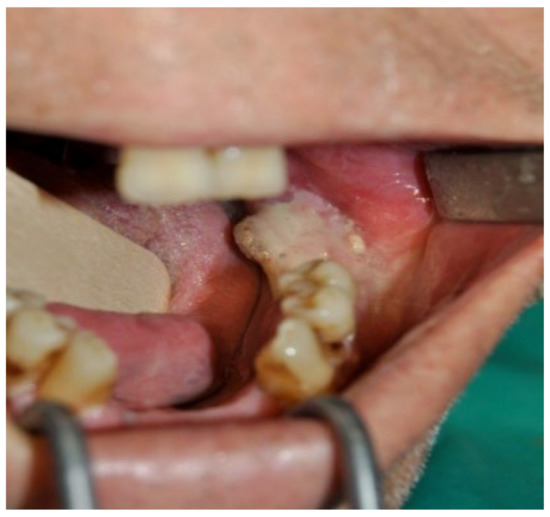

3.1. Clinical Case 1

3.2. Clinical Case 2

3.3. Clinical Case 3

3.4. Clinical Case 4

3.5. Clinical Case 5

3.6. Clinical Case 6